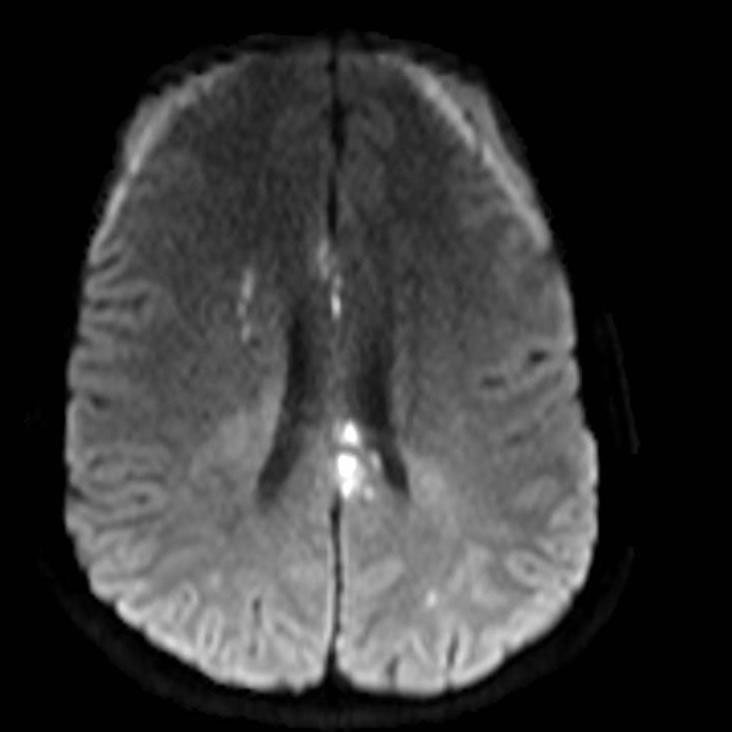

Noviembre 2024. Sanatorio Allende Paciente femenina de 16 años de edad sin antecedentes que consulta por síndrome confusional